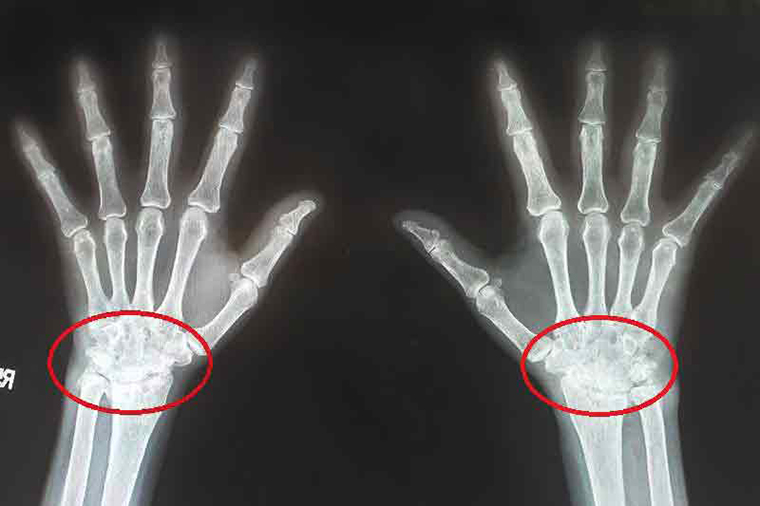

▲從劉女士手部X光片可看出骨骼結構破壞及變形,手腕動作受限,確診類風濕性關節炎。(圖/台北慈濟醫院提供)

【NOW健康 陳郁茹/新北報導】66歲的劉女士從事手工藝工作,手腕及手指關節長期不適,三不五時就感覺手腕腫痛、緊繃、無力,因此定期在骨科、復健科就診。最近因聽聞朋友確診類風濕關節炎,且與自己的症狀類似,因此在友人建議下至醫院求診,經醫師抽血發現,劉女士類風濕因子和發炎指數過高,且從手部X光片可看出骨骼結構破壞及變形,手腕動作受限,確診類風濕性關節炎,所幸在經藥物治療後,病情控制穩定,疼痛改善許多,發炎指數也恢復正常,目前得以正常生活。

類風濕性關節炎最常影響手指、手腕關節,發病初期關節會有緊繃感、晨間僵硬、腫痛無力,甚至連開門、擰毛巾、拿筆、拿筷子等基本生活技能都無法做到,要是遲遲未治療,可能造成骨頭侵蝕、肌腱斷裂、關節變形損傷,更甚者恐因自體免疫抗體的攻擊出現肺部纖維化、心包膜炎、神經病變、心血管病變、腎臟病等嚴重併發症,因此必須及早診治。